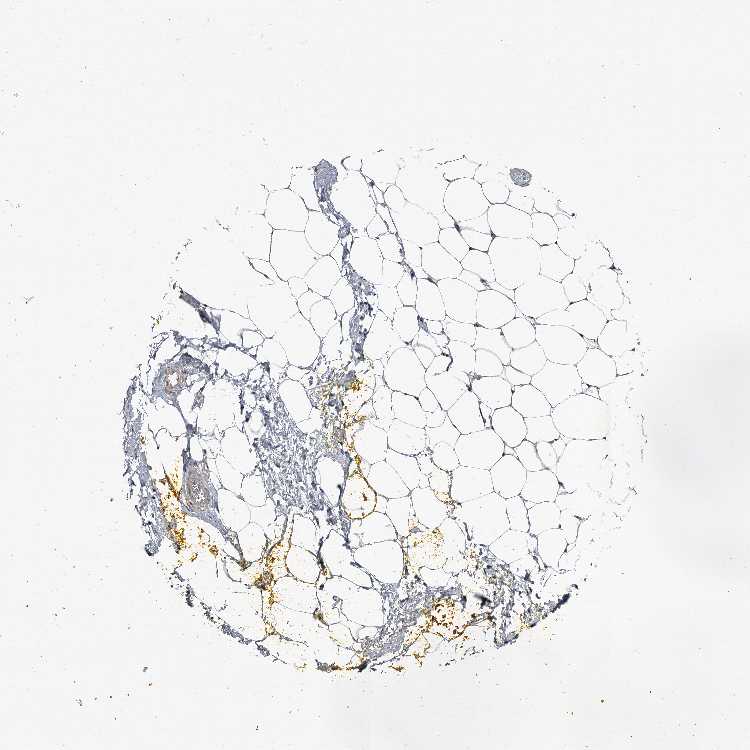

ADIPOSE TISSUE - Antibody stainingi

Antibody staining in the annotated cell types in the current human tissue is reported as not detected, low, medium, or high, based on conventional immunohistochemistry profiling in selected tissues. This score is based on the combination of the staining intensity and fraction of stained cells.

Each image is clickable and will lead to virtual microscopy that enables deeper exploration of all samples and also displays staining intensity scores, fraction scores and subcellular localization as well as patient and tissue information for each sample.

Antibody HPA038163Antibody HPA038164

Adipocytes Not detectedMedium